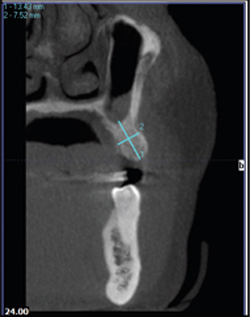

Along with a physical examination, an 8.9 second i-CAT® scan of the desired area is taken on the patient (Fig.1). There are 6 scan-size options ranging from single arch to full skull. Images are ready for viewing and use in 30 seconds.

The clinician can then proceed with diagnosis, evaluation, measurement, and treatment planning within i-CATVision™ software (Fig. 2).